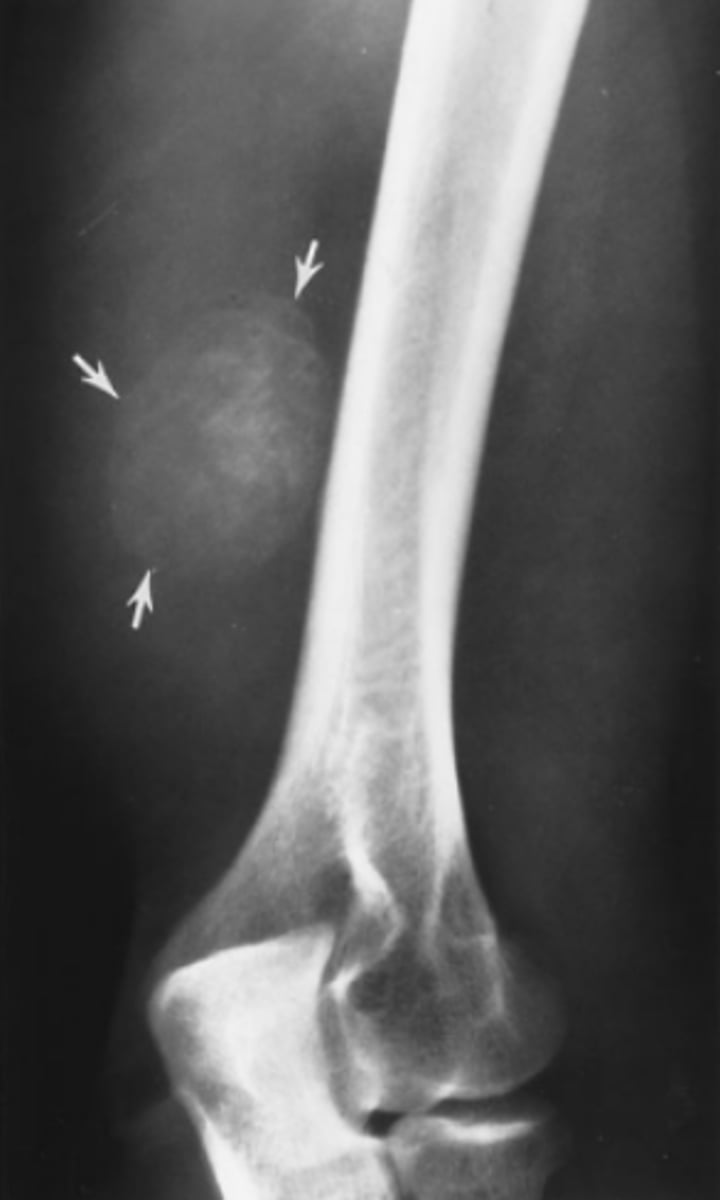

A 12-year-old girl comes to your pediatrics office complaining of 2 weeks of knee pain. There is no history of trauma. She is slightly swollen, tender, and erythematous over the proximal fibula. You obtain frontal

and lateral views of the tibia and fibula (AP and lateral views of the proximal tibia and fibula).

Based on the history, physical examination, and radi-

ographs for Case 6-6 (Figure 6-19), which of the following choices is the best working diagnosis?

A. A bone tumor, most likely benign

B. A bone tumor, most likely malignant

C. An infection of the bone

D. A stress fracture of the proximal fibula

Answer

A.

This is a focal lytic lesion in the proximal fibulat metadiaphysis with an intact shell of new cortex and a well defined zone of transition betweenitself and adjacent normal bone. Its benign!